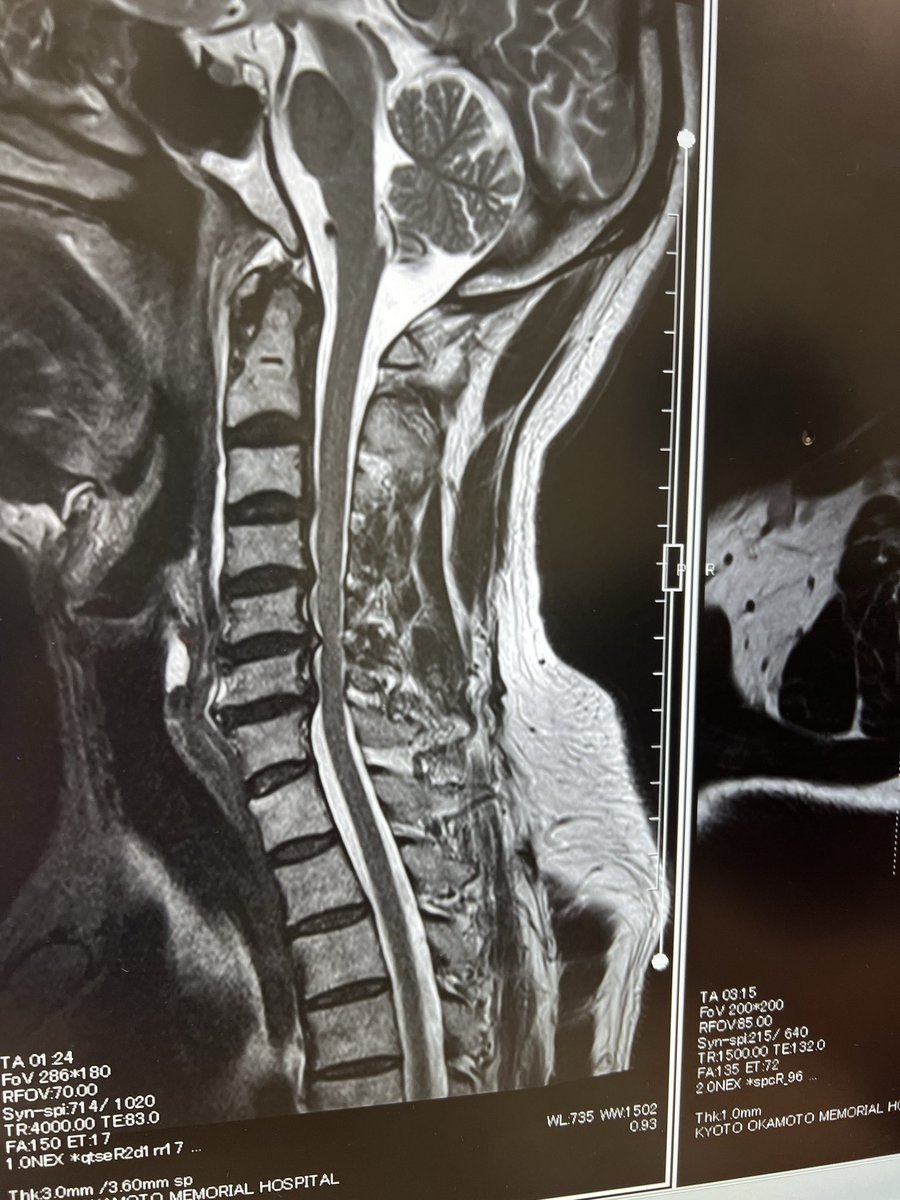

2020年27年ぶりにアマチュア再開局。3,5M〜1200MまでQRV。アマチュア無線家と繋がるのが楽しみ。また、気になったローカルな話題もお伝えしていきます。コマーシャルは、美容系なのでその情報もお伝えします。コマーシャル以外は、元バンドマン。2022年12月に脚立からの落下大腿骨骨折。只今リハビリ中。